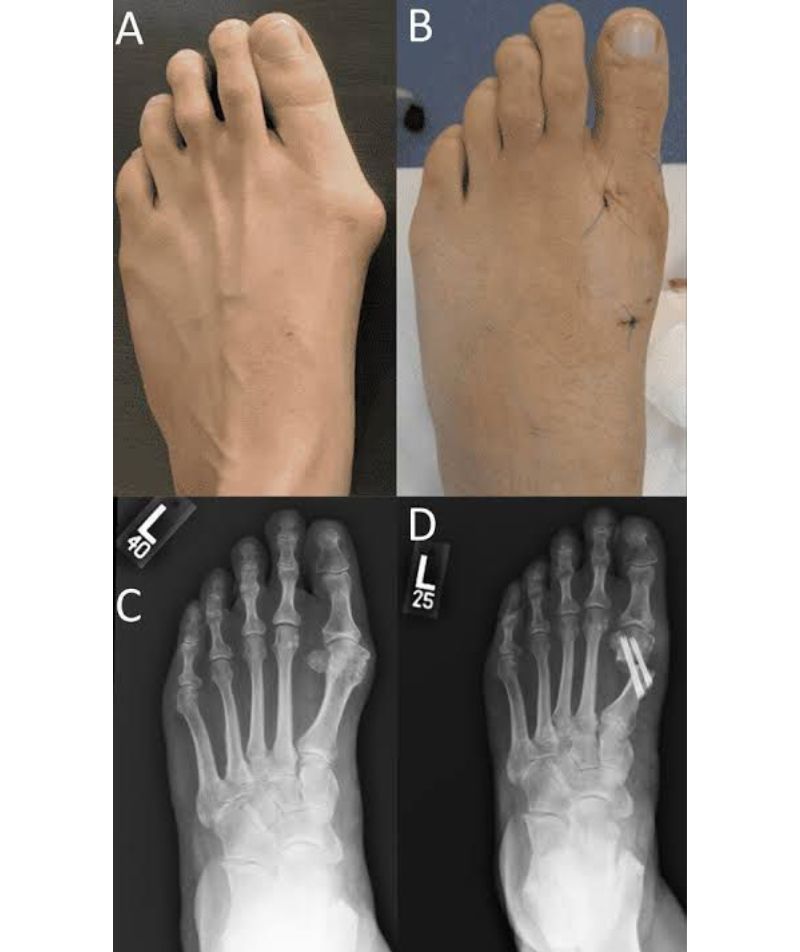

Typically thought of as a bump on the side of the toe’s. This may reflect changes in appearance of the alignment of the toe’s and also the anatomy. This happens overtime and has a genetic or hereditary component. It also is associated with patient of flat foot as well as people wearing tight shoes or pointed shoe’s. Symptoms felt by the patients range from pain, inflammation, swelling, redness and/or discomfort. Diagnosis is made by clinical and history taking and grading of severity over radiographs. Treatment mostly consists of conservative management which can be in the form of non- steroidal anti-inflammatory drugs, pads, spacers, exercises, shoe modifications and/or orthosis. When the severity is more surgical treatment is the only option. The goal of the surgery is not the cosmetic but the alignment of the toe’s.

- Minimally invasive bunion surgery (e.g., chevron osteotomy)

- Open reconstructive surgery in advanced or recurrent cases

- Precision diagnosis with weight-bearing X-rays and gait analysis

- Advanced surgical techniques (minimally invasive and open) for optimal correction